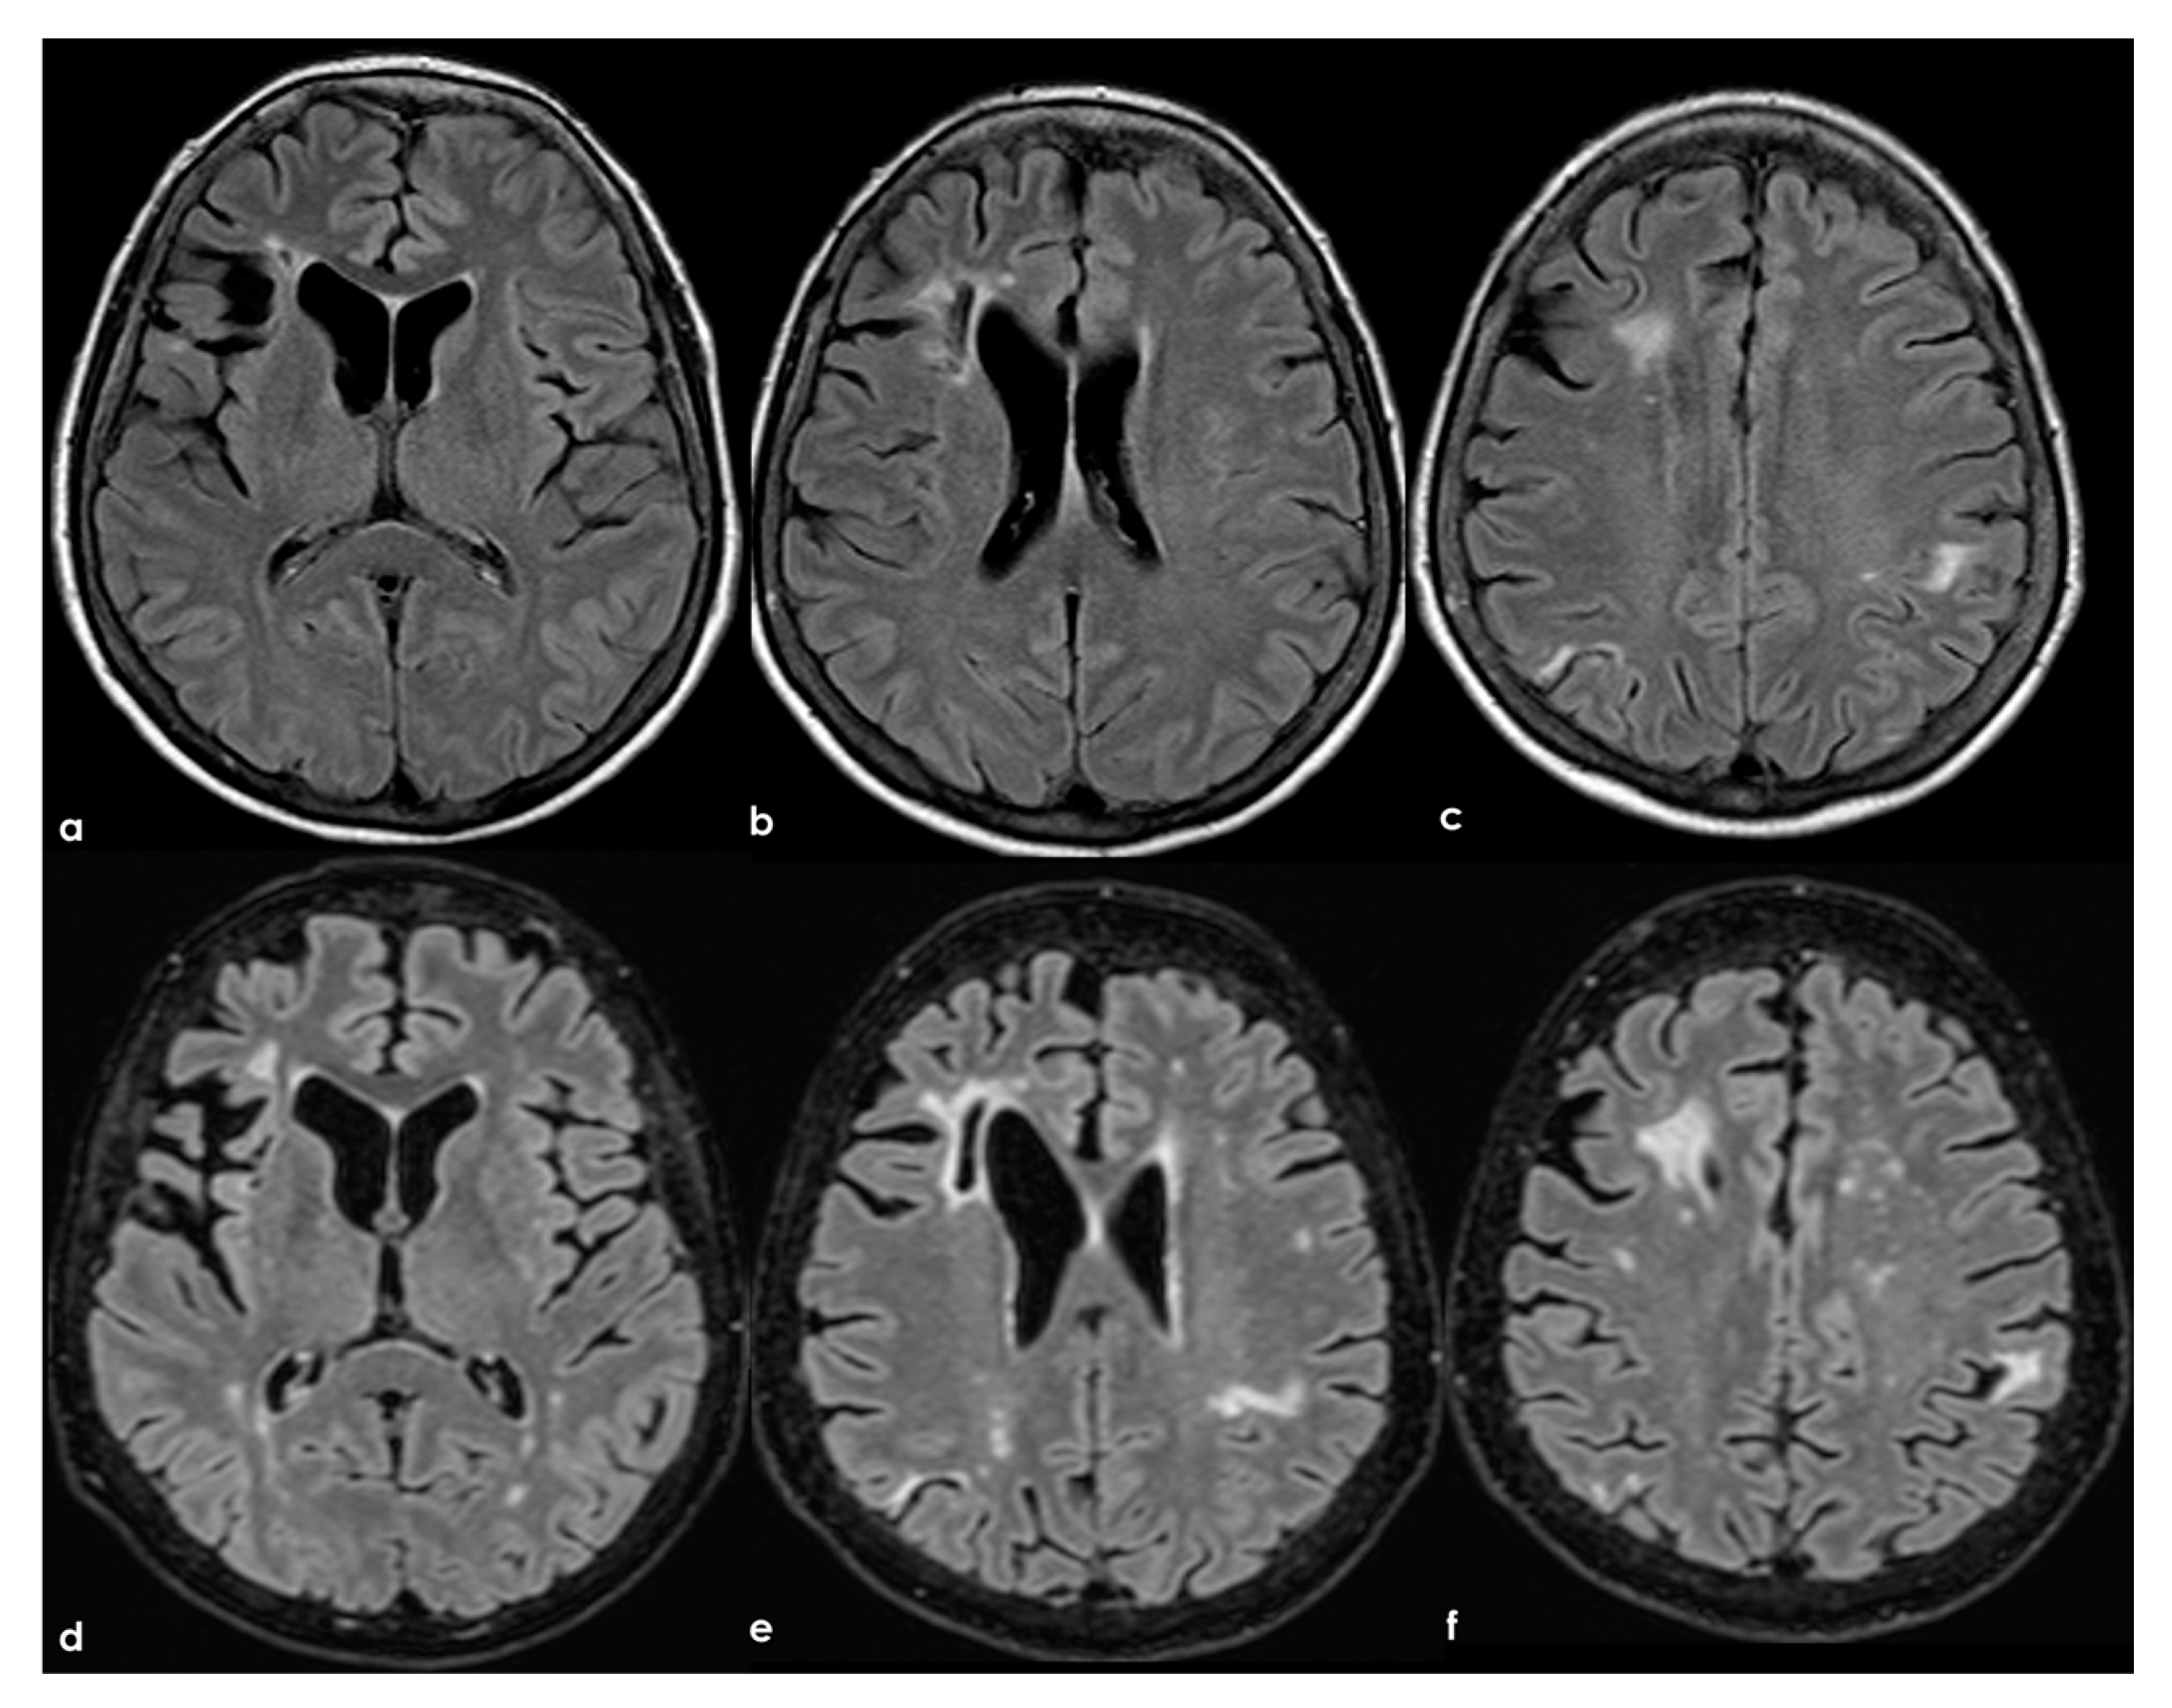

To date, as summarized by Hassan F et al. [], most studies investigating cognitive impairment in individuals carrying aPL and in those with APS have been limited by small sample sizes and significant variations in cognitive-impairment detection methods, the specific aspects of cognition assessed, and the types of antibodies examined (e.g., aCL, LA, or aβ2GPI), as well as the laboratory cutoffs used to define positivity []. In general, aPL carriers represent a highly heterogeneous group with substantial variability in the prognosis and risk of cognitive impairment. The absence of standardized methods for quantifying aPL, which may also change over time, and fluctuations in cutoff levels for positivity, pose challenges in comparing findings across different studies. APS can be secondary to autoimmune diseases, which can independently affect the CNS and contribute to cognitive impairment. Moreover, aPL antibodies are more commonly detected in the elderly population, among whom cognitive impairment and dementia are prevalent []. Consequently, the precise frequency and mechanisms of cognitive impairment in APS, their correlation with aPL activity, and the optimal approaches to diagnosis and treatment remain uncertain []. In fact, in a recent systematic review [] aiming to investigate the association between APS and cognitive dysfunction, the authors concluded that studies including neuroimaging biomarkers in APS/aPL-positive patients with cognitive dysfunction were scarce and heterogeneous; thus, multicenter studies with standardized image acquisition and international APS clinical and laboratory criteria are required. In Figure 2, an example of mild SVD involvement in a patient with APS (triple positivity) is proposed.

Figure 2.

Brain MRI (axial FLAIR in panels (a–d), coronal T2W in panels (a–g), and axial T2W in panel (h)) showing small punctate white-matter hyperintensities in the centrum semiovale, with a trend to watershed distribution (panel (d)), and a mild increase in enlarged perivascular spaces in the subcortical white matter (panels (e–h)).